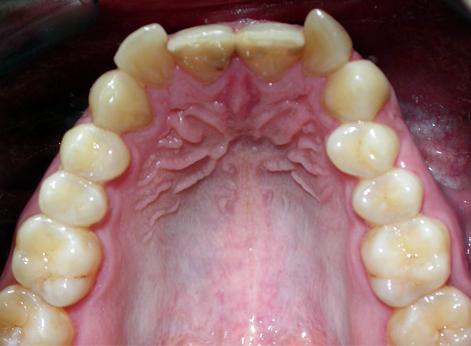

Результат получен спустя 18 месяцев после начала лечения

Лечение проводилось с апроксимальной сепарацией эмали зубов. Применялись керамические брекеты.